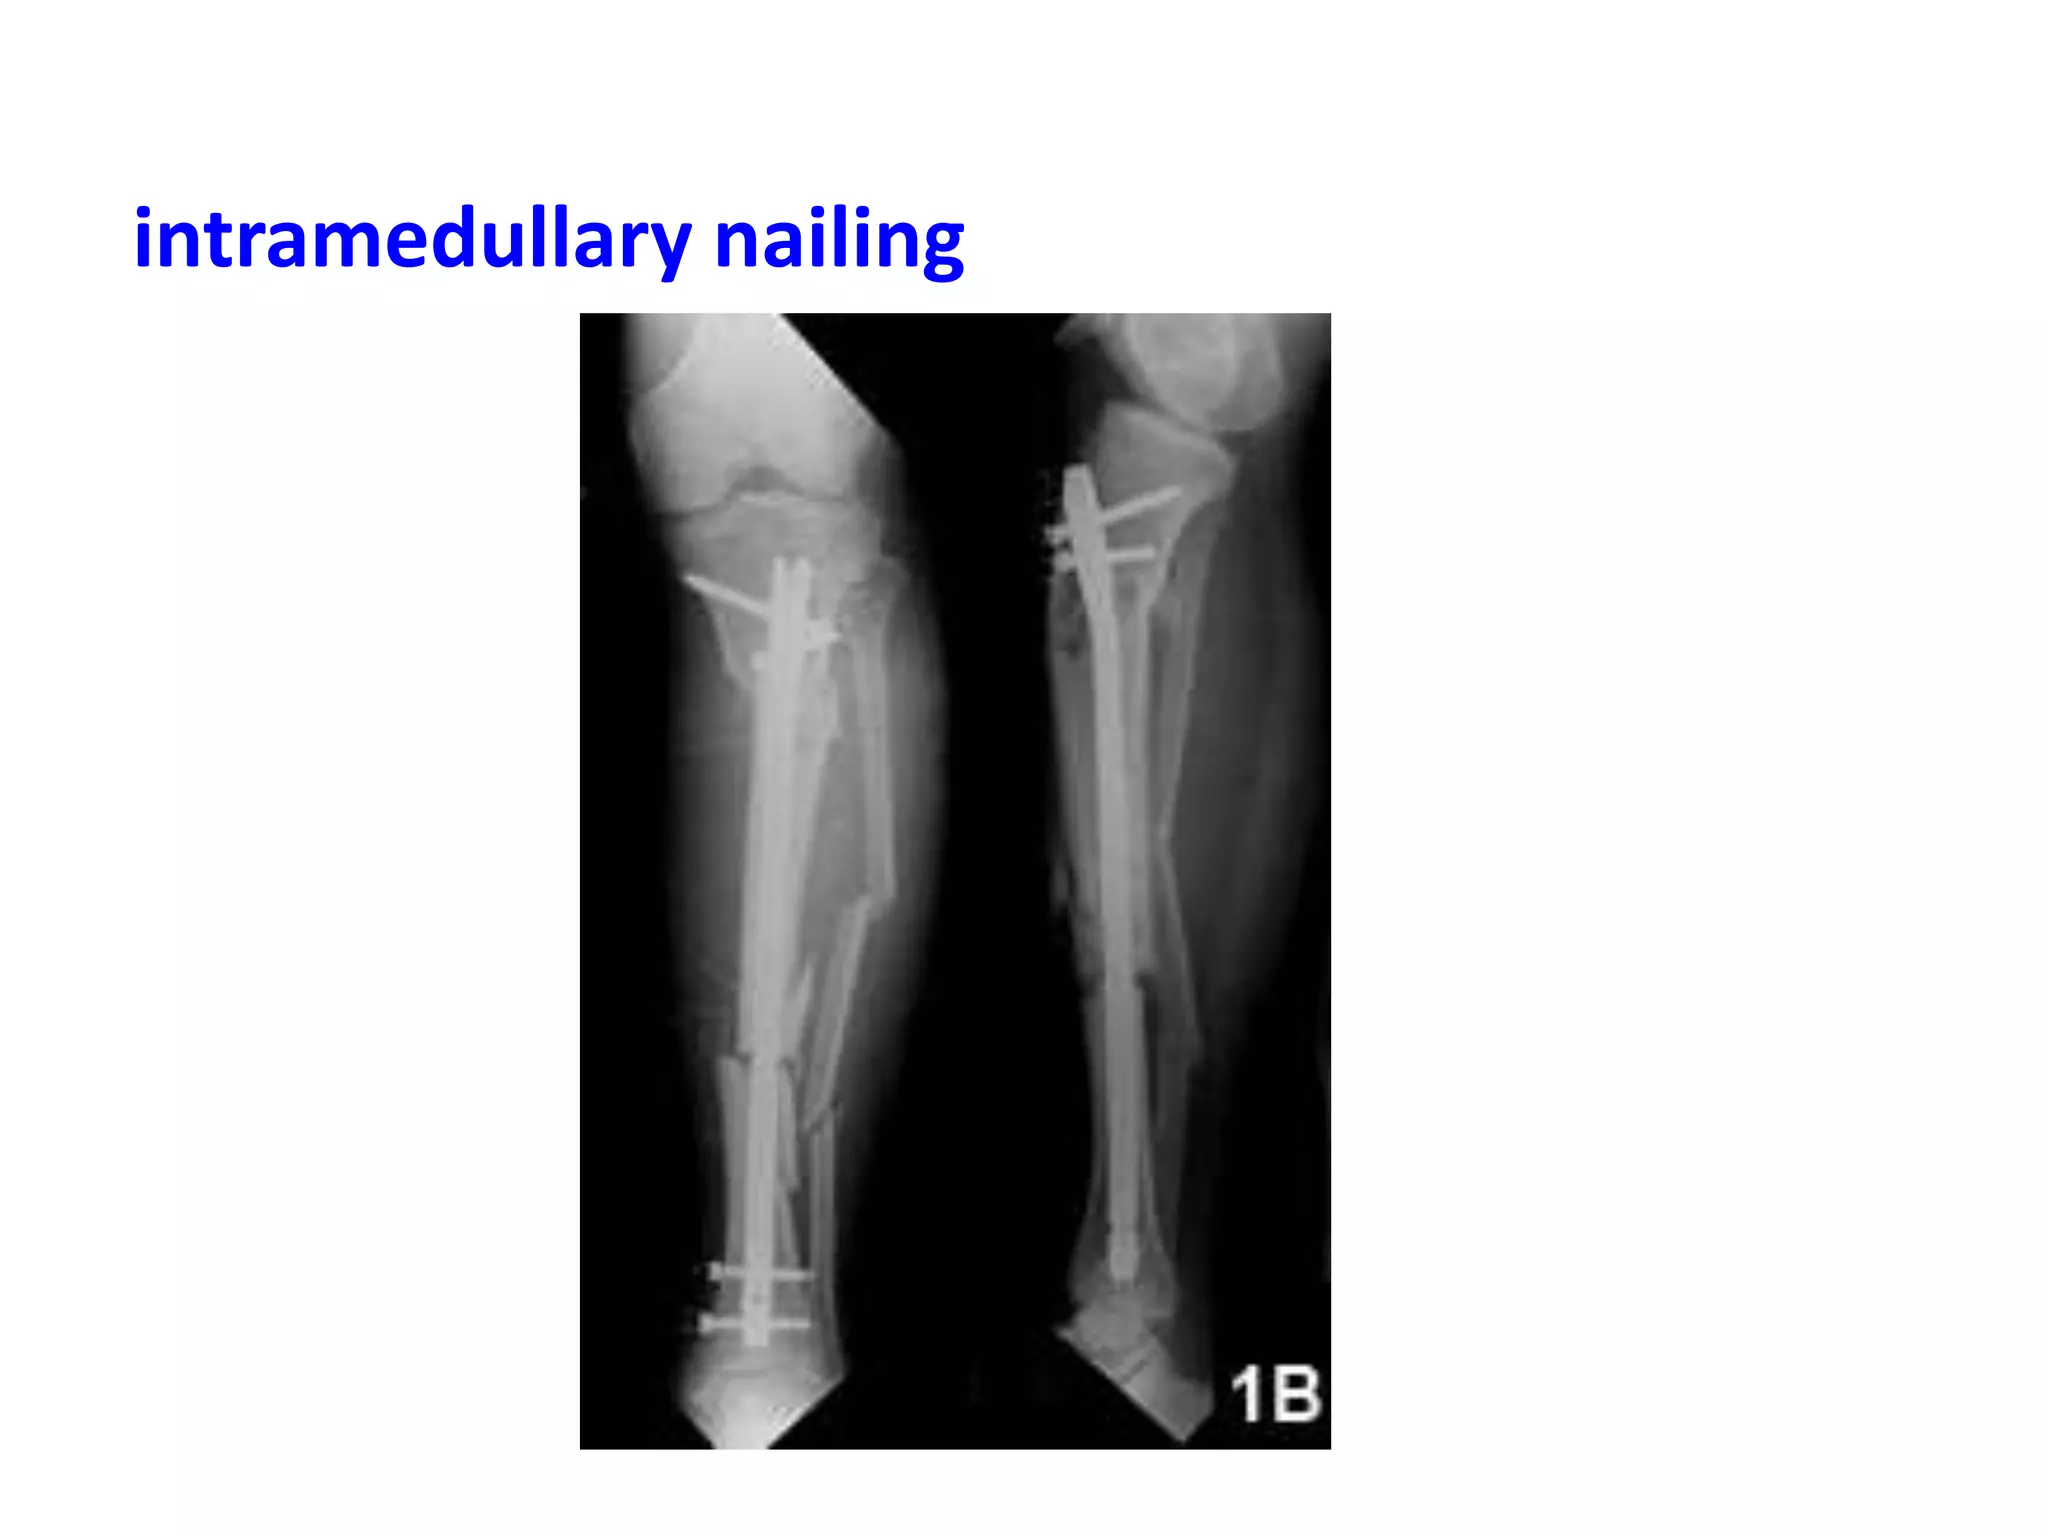

intramedullary nailing

Methods of relativestability Bridging plate